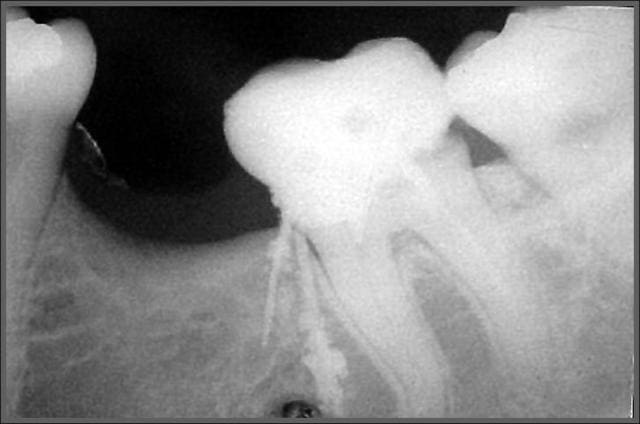

Tiens en parlant d'honneur la je meriterais un grand doigt.

Protaper dans la racine mesiale, amlg dans la racine distale, Mais j'ai mis la digue :p.

Conclusion RAS au controle a 1 an !

Comme dit Stéphane tous les moyens sont bons tant qu on arrive au résultat escompté ;p